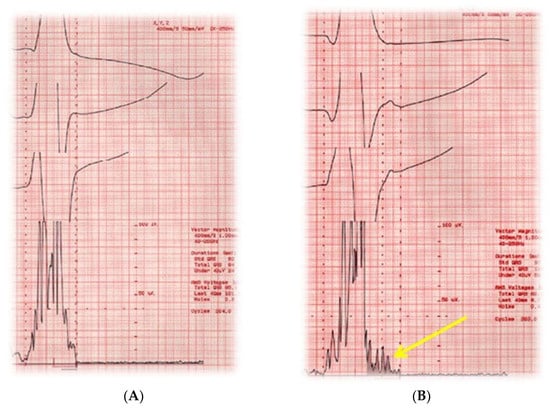

Signal-averaged electrocardiography (SAECG) is a method to improve the signal-to-noise ratio of a surface electrocardiogram, thus facilitating the identification of low-amplitude signal at the end of QRS complex (Figure 4) [73].

This test was initially found to be a promising marker of SCD in patients with ischemic cardiomyopathy, and later in patients with non-ischemic cardiomyopathy [74]. Nevertheless, subsequent studies have shown conflicting and less promising results. A more recent study performed, comparing 123-mIBG to SAECG, showed that 123-mIGB, and not SAECG, was a predictor of SCD in patients with mild to moderate systolic dysfunction [51].

However, SAECG has a high negative predictive value (normal SAECG is associated at risk <5% on inducible ventricular tachycardia at the electrophysiology study). For this reason, SAECG may be used as the first-line test to identify patients at low risk of SCD.

Figure 4. Signal-average ECG of a normal subject (A) and a patient with idiopathic dilated cardiomyopathy (B). Note the fragmentation of terminal parts of QRS indicative of late potentials (yellow line).